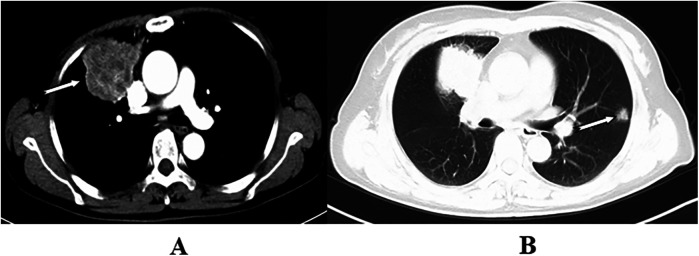

Background and objective: The increased use of chest CT for clinical diagnosis and screening has improved the detection of early-stage lung cancer and the identification of bilateral lung lesions. Despite this, consensus on the feasibility of simultaneous vs. staged bilateral surgery for patients with bilateral lesions remains elusive, necessitating further investigation. This study assessed the safety, feasibility, and health-economics value of simultaneous bilateral pulmonary surgery by comparing perioperative clinical indicators and medical costs with those of unilateral surgery and simulated staged bilateral surgery.

Methods: A retrospective analysis was conducted using clinical data from 78 patients who underwent simultaneous bilateral pulmonary surgery at the Lung Cancer Center of West China Hospital of Sichuan University by the same medical team from January 2016 to October 2024. An equal number of patients who underwent unilateral surgery during the same period served as controls. Perioperative indicators were compared between these groups, and medical expenses were assessed against those of a second control group undergoing simulated staged surgery.